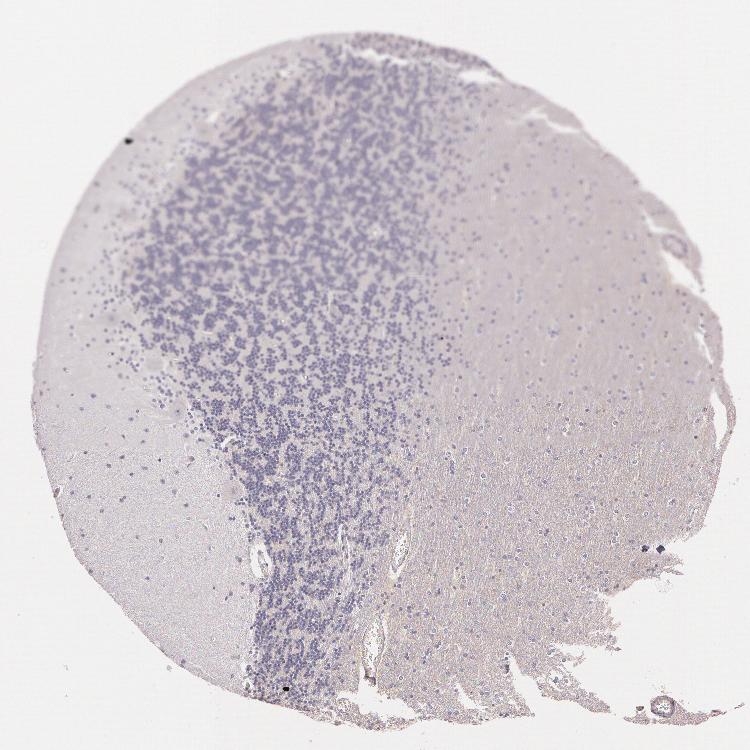

CEREBELLUM - Antibody stainingi

Antibody staining in the annotated cell types in the current human tissue is reported as not detected, low, medium, or high, based on conventional immunohistochemistry profiling in selected tissues. This score is based on the combination of the staining intensity and fraction of stained cells.

Each image is clickable and will lead to virtual microscopy that enables deeper exploration of all samples and also displays staining intensity scores, fraction scores and subcellular localization as well as patient and tissue information for each sample.

Antibody HPA001601

Purkinje cells Not detected

Cells in granular layer Not detected

Cells in molecular layer Not detected